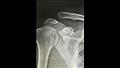

خضع الفنان محمود حجازي لعملية جراحية في كتفه، اليوم الأثنين.

ونشر حجازي صورًا له داخل أحد المستشفيات، عبر حسابه الرسمي بموقع "إنستجرام"، وعلق :" الحمد لله عملت عملية النهاردة كان التوقيت صعب جدا عشان كان بقالي ٥ أيام كتفي مخلوع وأنا بصور بيه وماعنديش إجازة ولسه بصور بس الحمد لله على كل شئ العملية نجحت وهخرج النهارده وهكمل تاني تصوير من بكره إن شاء الله استكمالا للانتهاء من الأعمال الرمضانية".